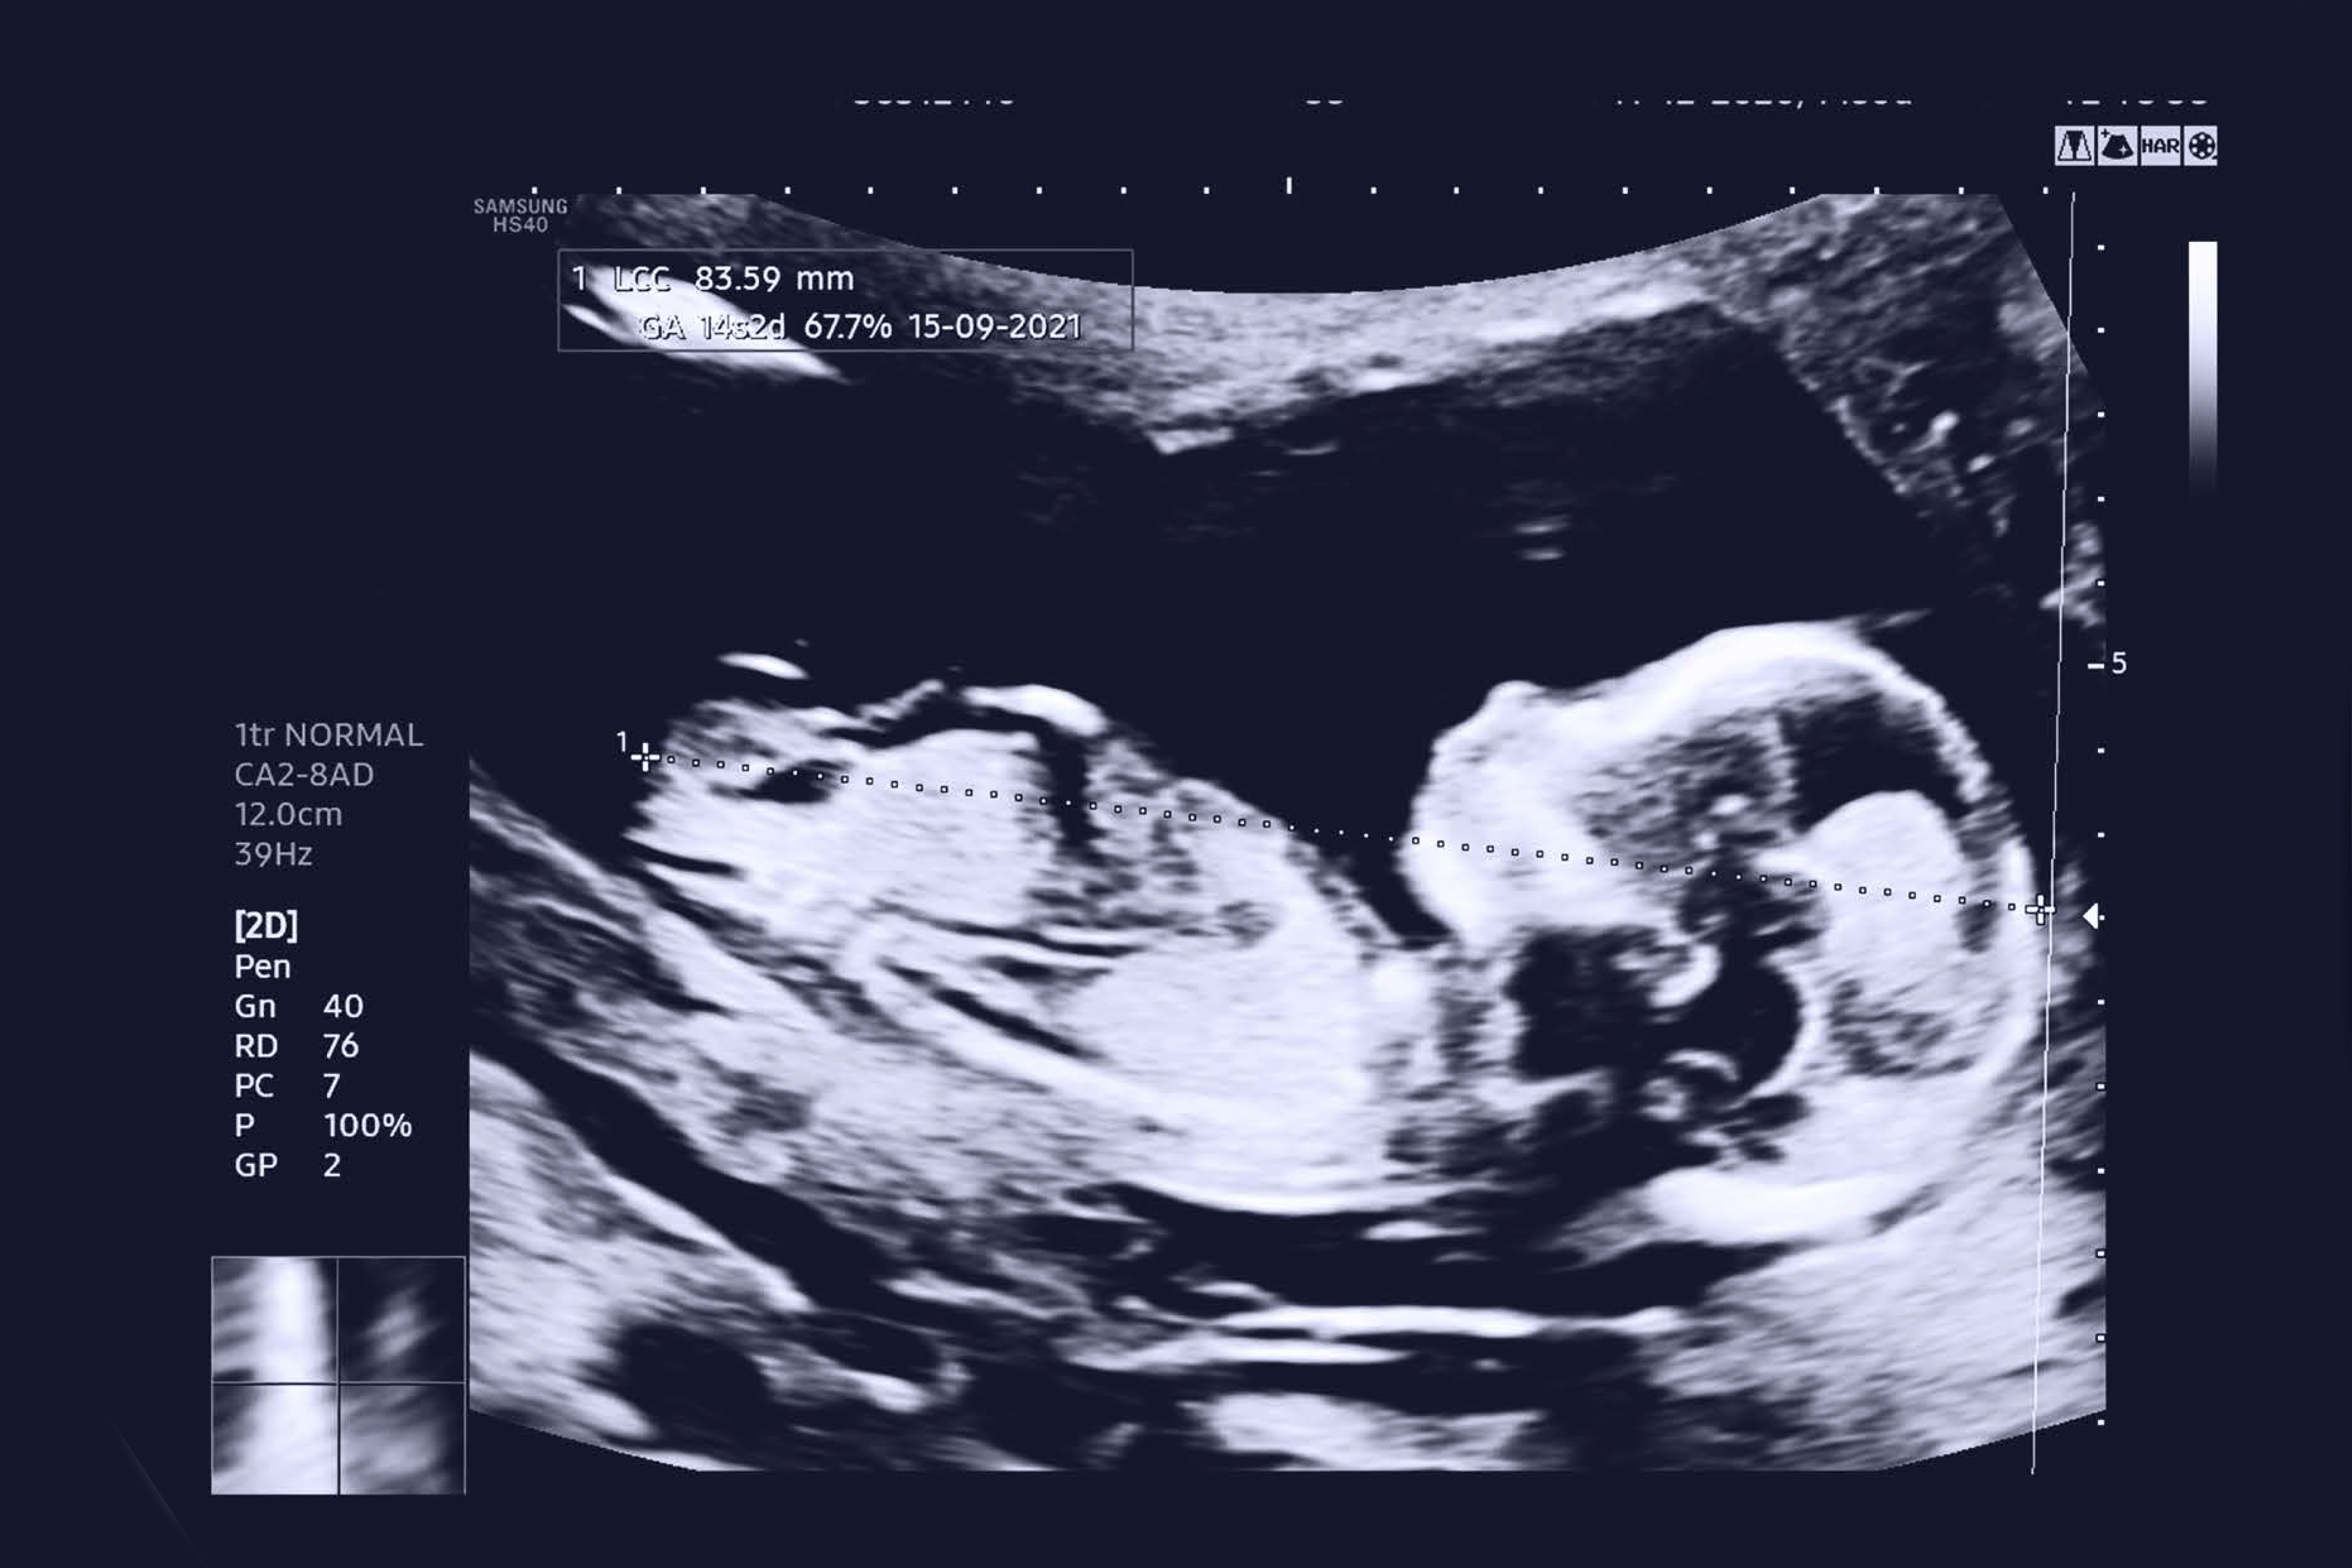

Marcadores ecográficos: a esta edad gestacional el embrión mide entre 4.5 a 8.4 centímetros, pero gracias a los equipos de ecografía con que hoy se cuenta es posible evaluar la talla exacta, el líquido que existe detrás del cuello (translucencia nucal), la presencia o ausencia del hueso nasal, la circulación en el corazón y en algunas venas y arterias, además del examen de la anatomía fetal.